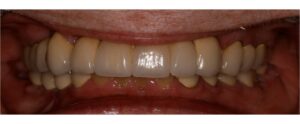

Η Προσθετικη οδοντιατρικη ειναι ο κλαδος της οδοντιατρικης που ασχολειται με την αποκατασταση μεγαλης η μικρης νωδοτητας στον οδοντικο φραγμο.

Η Προσθετικη Οδοντιατρικη χωριζεται σε

- Ακινητη προσθετικη, δηλαδη στεφανες και γεφυρες

- Κινητη προσθετικη, δηλαδη μερικες και ολικες οδοντοστοιχιες

- Προσθετικη επι εμφυτευματων